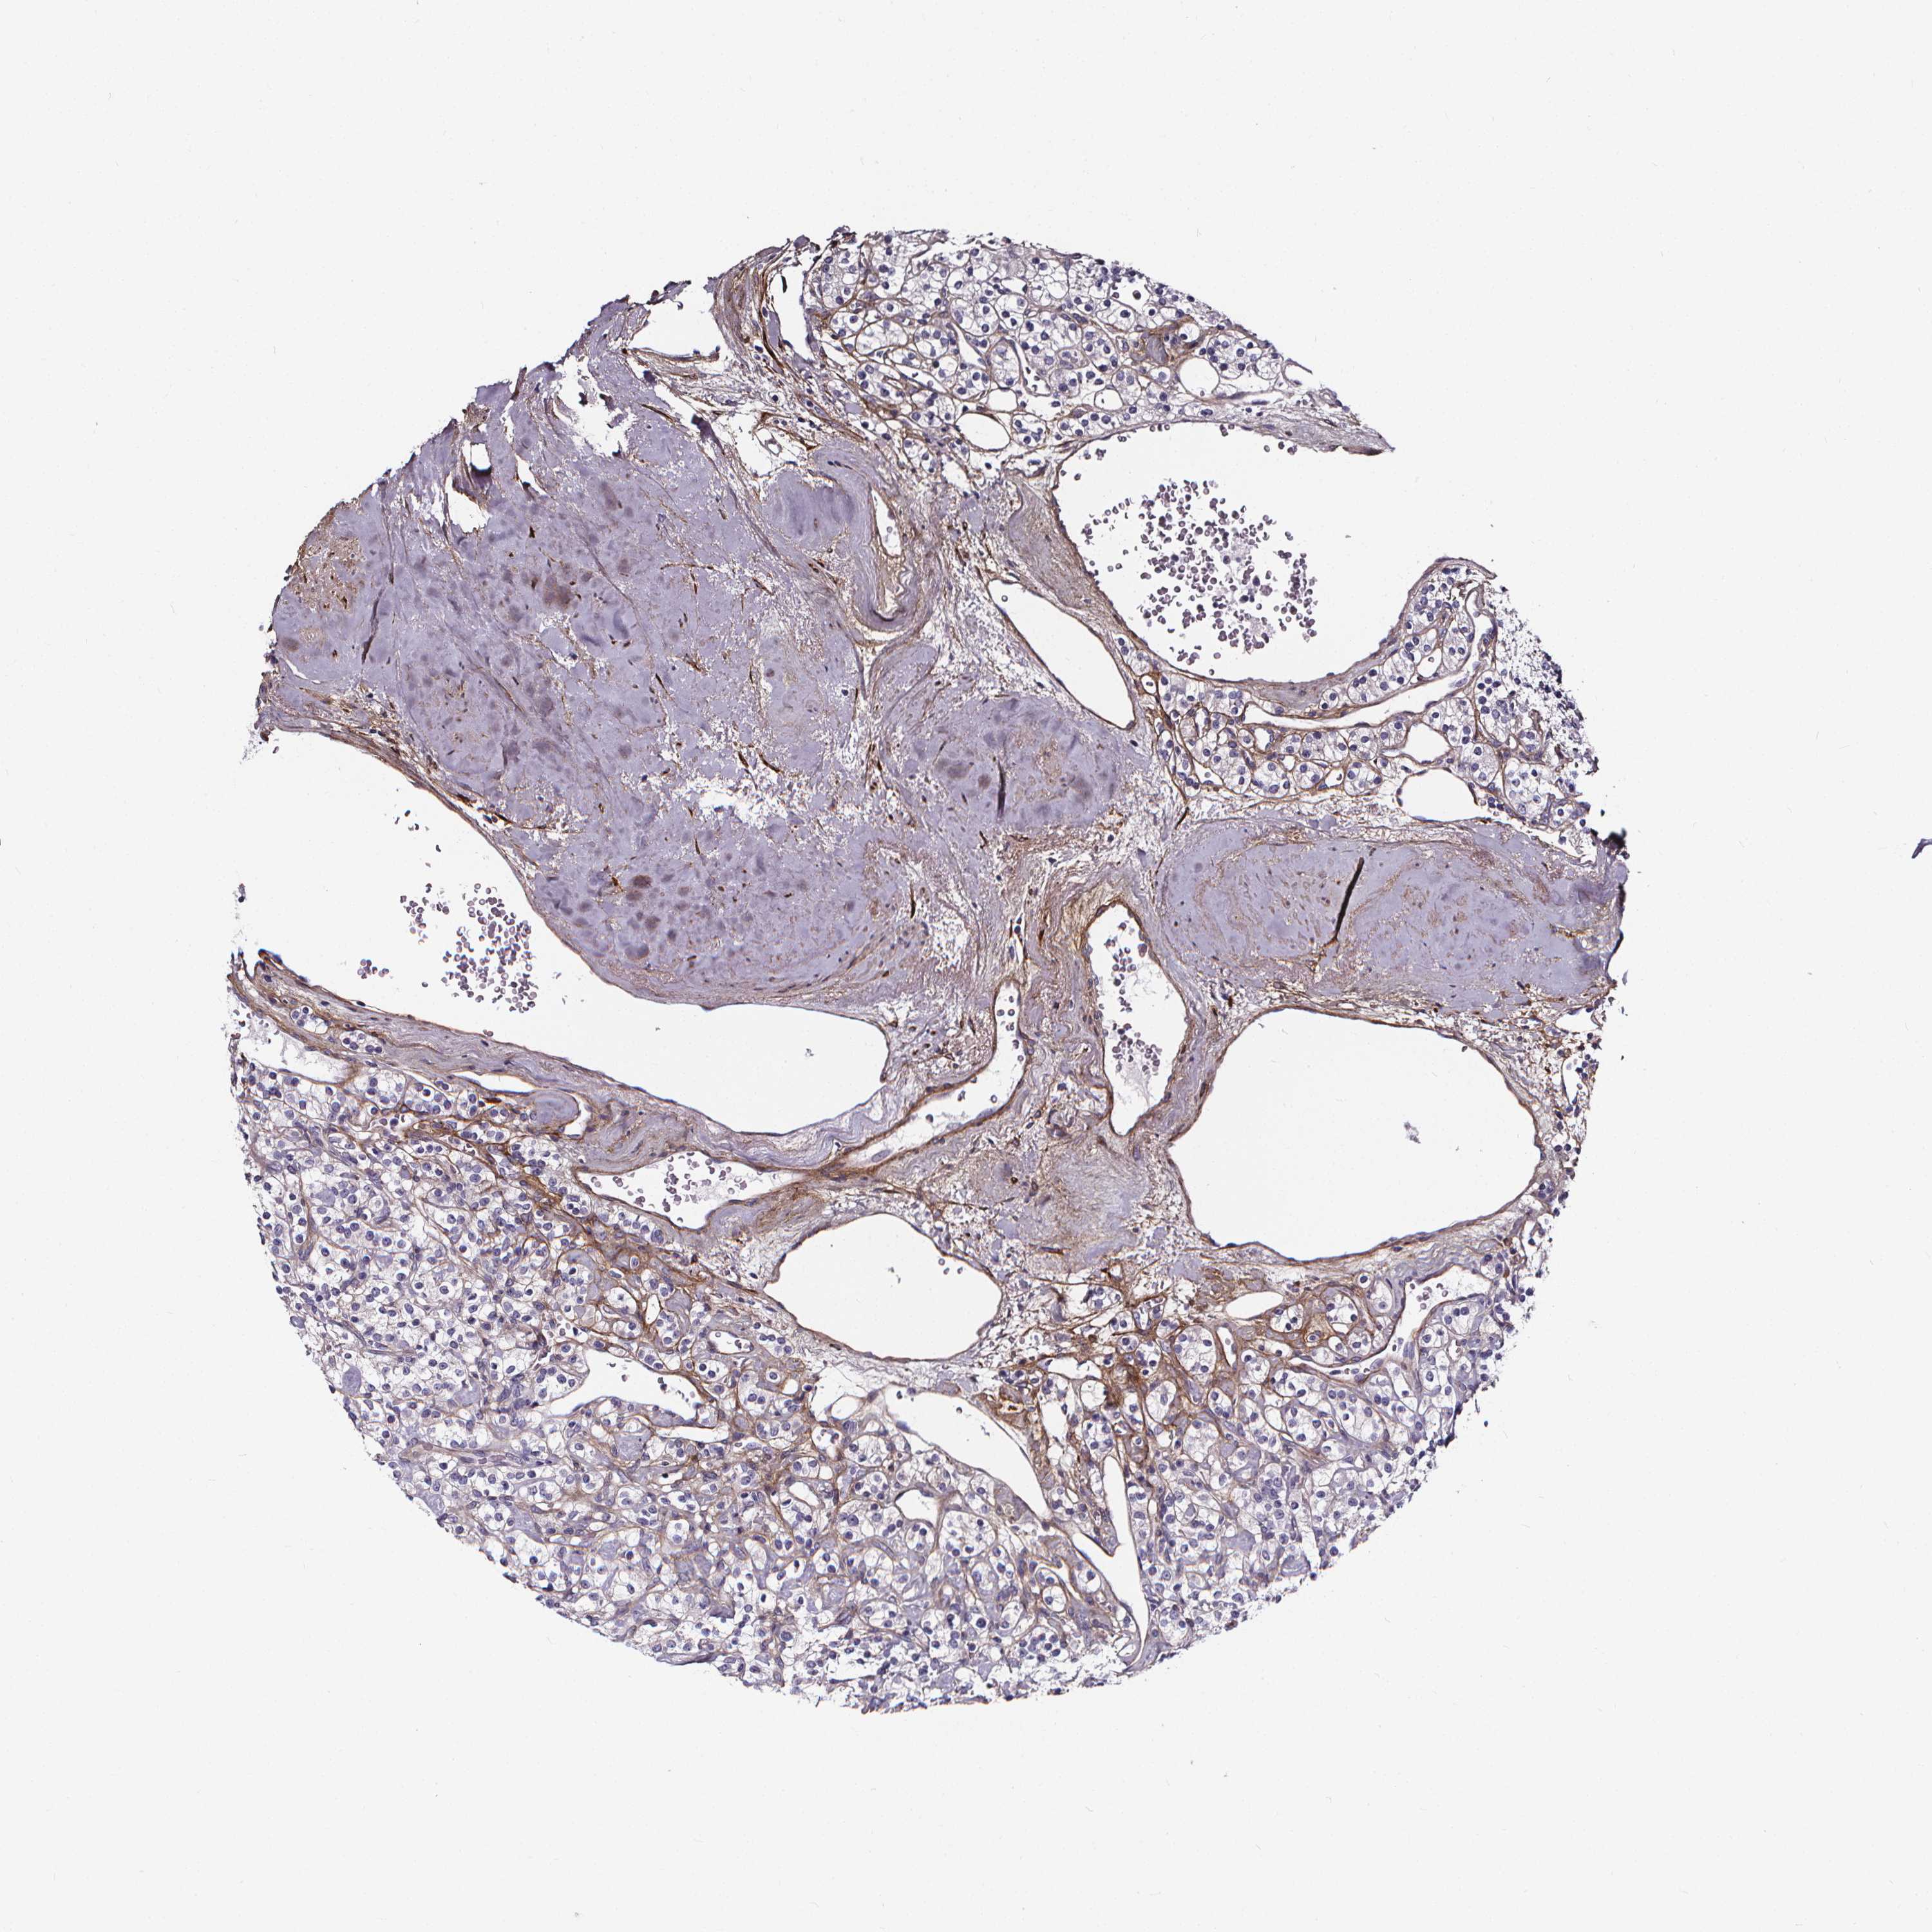

KIDNEY RENAL CLEAR CELL CARCINOMA (VALIDATION) - Interactive survival scatter ploti

The Survival Scatter plot shows the clinical status (i.e. dead or alive) for all individuals in the patient cohort, based on the same data that underlies the corresponding Kaplan-Meier plots. Patients that are alive at last time for follow-up are shown in blue and patients who have died during the study are shown in red.

The x-axis shows the expression levels (FPKM) of the investigated gene in the tumor tissue at the time of diagnosis. The y-axis shows the follow-up time after diagnosis (years). Both axes are complimented with kernel density curves demonstrating the data density over the axes. The top density plot shows the expression levels (FPKM) distribution among dead (red) and alive patients (blue). The right density plot shows the data density of the survived years of dead patients with high and low expression levels respectively, stratified using the cutoff indicated by the vertical dashed line through the Survival Scatter plot. This cutoff is automatically defined based on the FPKM cutoff that minimizes the p-score. The cutoff can be changed by dragging the vertical line or by entering a cutoff value in the square labeled "Current cut-off".

Under the Survival Scatter plot the p-score landscape (black curve; left axis) is shown together with dead median separation (red curve; right axis). Dead median separation is the difference in median mRNA expression between patients who have died with high and low expression, respectively. It is calculated as follows: median FPKM expression of dead patients with high expression - median FPKM expression of dead patients with low expression. This is intended to aid the user in visually exploring custom cutoffs and the associated p-scores and dead median separation.

Individual patient data is displayed and can be filtered by clicking on one or more of the category buttons on the top of the page. Categories describing expression level and patient information include: high, low, alive, dead, female, male and tumor stages. The scale of the x-axis can be toggled between linear and log-scale by clicking on the "x log" button. Mouse-over function shows TCGA ID, patient information and mRNA expression (FPKM) for each patient.

& Survival analysisi

Kaplan-Meier plots summarize results from analysis of correlation between mRNA expression level and patient survival. Patients were divided based on level of expression into one of the two groups "low" (under cut off) or "high" (over cut off). X-axis shows time for survival (years) and y-axis shows the probability of survival, where 1.0 corresponds to 100 percent.

AEBP1 is not prognostic in Kidney Renal Clear Cell Carcinoma (validation)

Best expression cut offi

Based on the FPKM value of each gene, patients were classified into two groups and association between prognosis (survival) and gene expression (FPKM) was examined. The best expression cut-off refers the FPKM value that yields maximal difference with regard to survival between the two groups at the lowest log-rank P-value. Best expression cut-off was selected based on survival analysis .

When clicking on this number, the vertical dashed line indicating cut-off, the interactive survival plot, and the Kaplan-Meier curve will be adjusted to show results based on the best expression cut-off.

: 18.39

P scorei

Log-rank P value for Kaplan-Meier plot showing results from analysis of correlation between mRNA expression level and patient survival.

N/A

TCGA RNA samplesi

RNA-seq data is reported as average FPKM (number Fragments Per Kilobase of exon per Million reads), generated by the The Cancer Genome Atlas (TCGA) .

Normal distribution across the dataset is visualized with box plots, shown as median and 25th and 75th percentiles. Points are displayed as outliers if they are above or below 1.5 times the interquartile range. FPKM values of the individual samples are presented next to the box plot.

Average pTPM 167.2

Number of samples 100